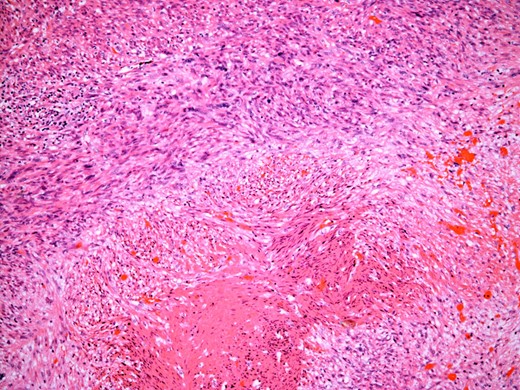

At the time of referral, the lesion had dramatically increased in size and become more symptomatic, therefore surgical excision was agreed. He underwent a trans-scrotal right epididymectomy where an irregular white mass measuring 15 × 46 × 35 mm3 was excised. Histological examination demonstrated a well delineated mass comprising fascicles of cytologically malignant spindle cells (Fig. 2). These showed moderate to nuclear pleomorphism, frequent mitotic figures, including atypical forms, and zones of coagulative necrosis (Fig. 3). Immunohistochemistry showed the tumour cells were strongly and diffusely positive for desmin, smooth muscle actin and h-caldesmon. FISH analysis for MDM2 amplification excluded a dedifferentiated liposarcoma, the main differential diagnosis at this site. Overall, the features were those of a paratesticular LMS, which was FNCLCC/Trojani grade 2.

The tumour comprises fascicles of atypical spindle cells showing prominent cytological atypia and nuclear pleomorphism. Zones of coagulative tumour cell necrosis are present.

On higher power, severe cytological atypia is evident, with frequent mitotic figures including atypical mitotic forms.